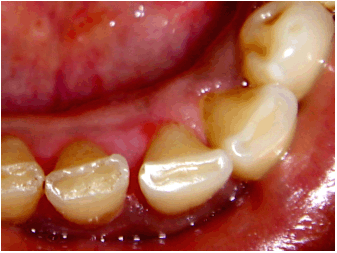

An intraoral examination revealed generalized pink gingiva with a well-demarcated, non-tender, firm, focal, sessile nodular growth arising from the interdental papilla of the mandibular right central and lateral incisors lingually. Owing to the pressure from the tongue, the lesion has progressively become flat in appearance. The oval-shaped mass was 2.5x3 cm in size, with a reddish pink color, smooth surface, and distinct edges (Figure 1). Bleeding on probing was noted. Clinically, differential diagnoses for the growth were pyogenic granuloma, peripheral odontogenic fibroma, fibroma and peripheral giant cell granuloma. Because of patient's sex, age, location, colour and consistency of the lesion, a provisional diagnosis of pyogenic granuloma was made for the gingival growth. Oral hygiene instructions were given to the patient and oral prophylaxis was done. After two weeks, the growth was excised conservatively to prevent the development of an unsightly gingival defect in the anterior maxilla, followed by root planing and curettage (Figure 2). The excised tissue was sent for histopathologic examination. The excised tissue was oval, 2.5x3 cm in size, reddish pink and firm in consistency on inspection. While grossing the tissue, slight grittiness was felt. The patient was called after one week for removal of dressing and showed uneventful healing. After six months, recurrence of the growth was not observed (Figure 3).

Figure 1: Pre-operative picture showing well-demarcated, non-tender, firm, focal, sessile nodular growth.